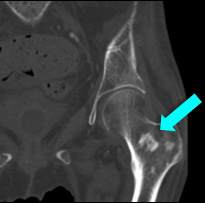

CTの骨条件では、頭蓋骨に不均一な骨硬化像を認める。

<骨病変>

• 大腿骨遠位と脛骨近位に左右対称性の骨硬化

• 骨シンチグラフィーで強い集積